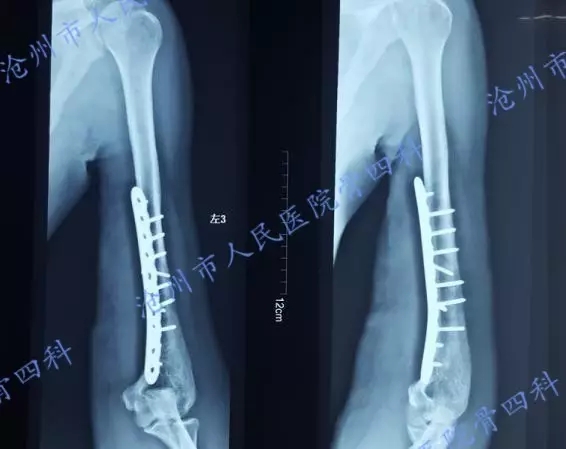

术后复查X光片示:骨折复位及内固定位置良好。

患者术后1周,患肢血运良好。取双下肢腓肠神经移植于左上肢尺神经及正中神经缺损处,肱骨远端骨折处予钛板螺钉牢固固定。创面更换VSD负压吸引。